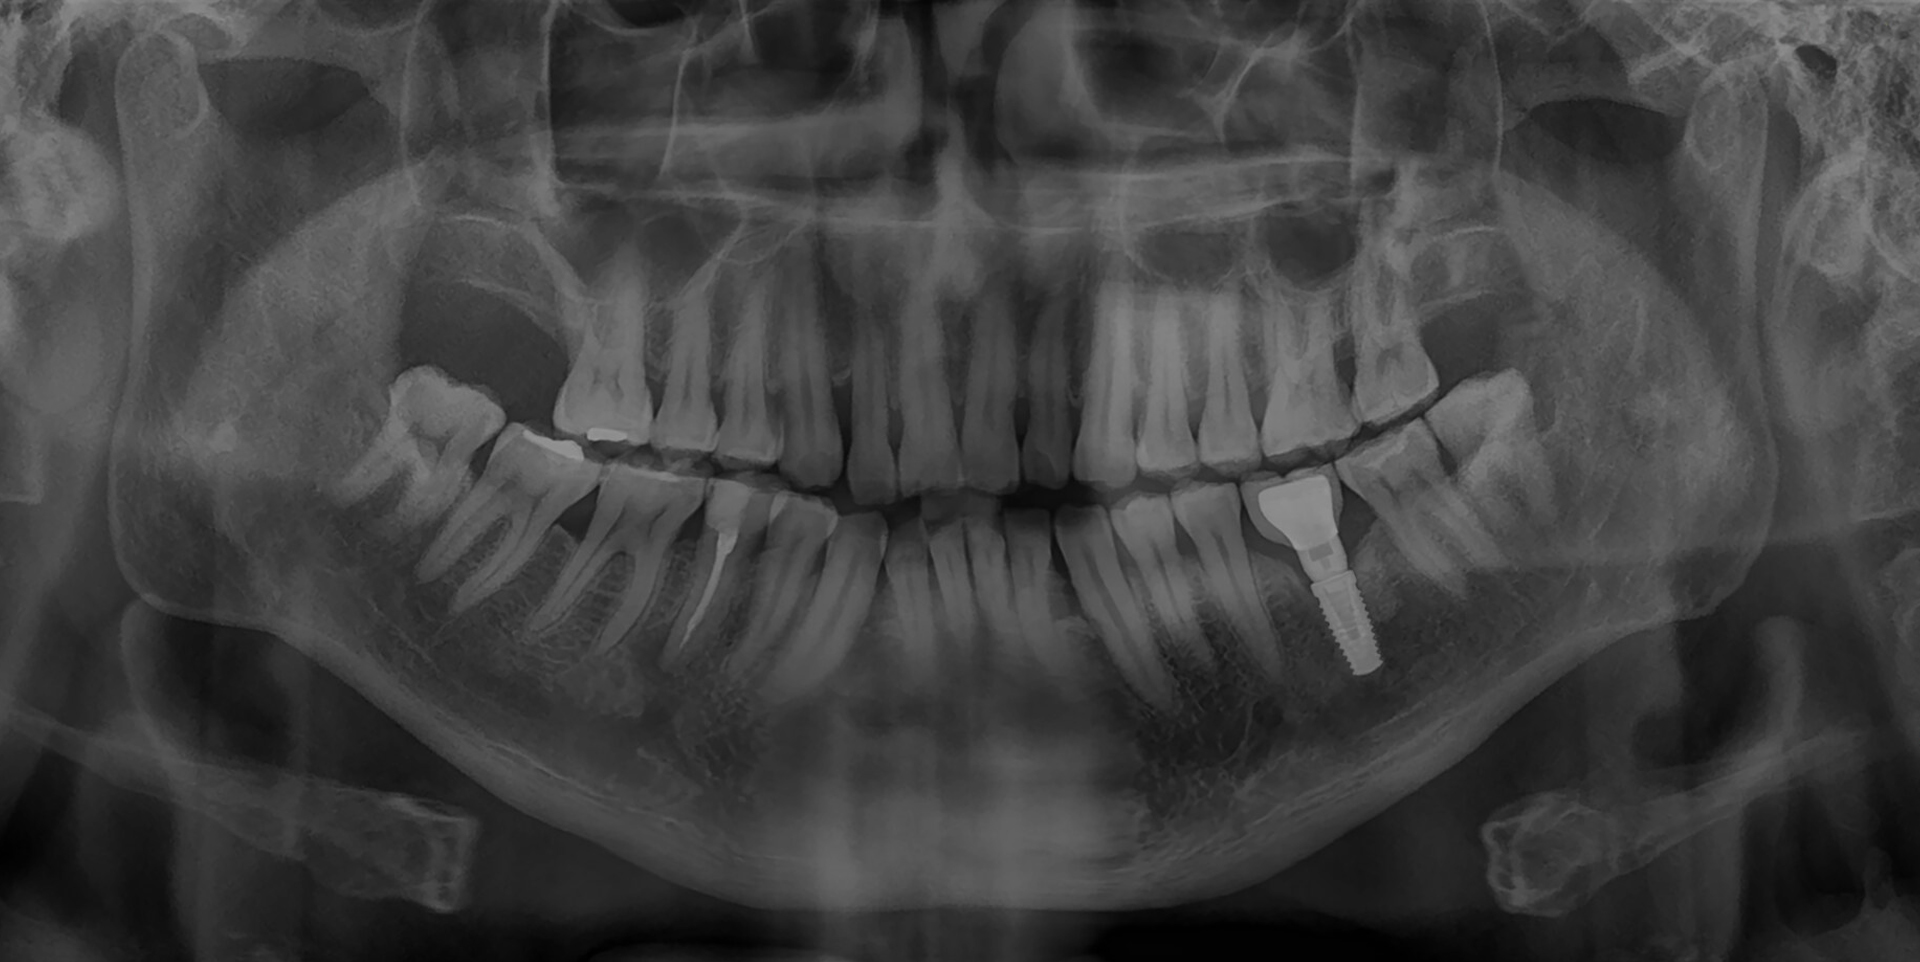

We begin by administering either a local or general anesthetic to numb the area or put you into a sleep-like state. We then make a small incision through the gums and insert the titanium implant post deep into the bone of the jaw. The implant site is given time to heal, and will naturally fuse with the bone in about six months. After this time, we’ll create new restorations for your smile that will attach to or snap onto the implant. Your implant can last for several decades without showing any signs of wear or damage.